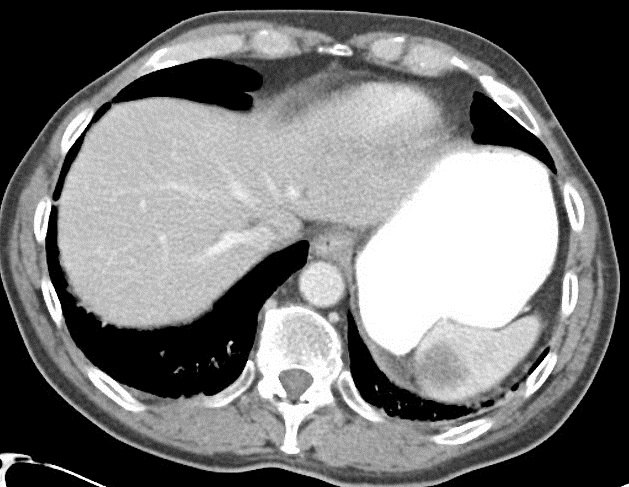

Image radiologique TDM en coupe axial

d'une autre lymphome Hodgkinien maligne de la rate

avec aspect lesionel des nodules ovalaires

hypodensite en rapport de parenchyme de la rate .

Lesions sont en s'observer facile au phase de veine

porte |